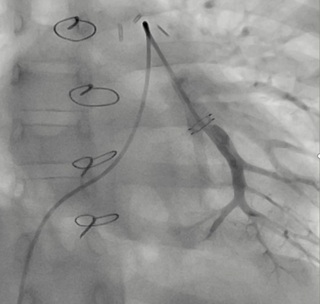

Catheterization was naturally indicated for managing his condition. We first performed an ultrasonic evaluation of his femoral veins to ensure they had at least a 3 mm axial diameter. After securing vascular access, angiographic verification of the right femoral vein patency and diameter was performed. We conducted a standard diagnostic hemodynamic catheterization under fluoroscopic control in a biplane system (Artis Zee, Siemens®) with a low dose protocol. Then, pump injection with diluted contrast (0.5 ml of isosmolar contrast per kg of body weight, diluted with isotonic saline solution in a 70% contrast to 30% saline ratio) into the left pulmonary artery was achieved with biplanar acquisition at 15 images per second (Figures 1 & 2). This process was to examine the left lung pulmonary arterial architecture to find an ideal implantation site, requiring a length of at least 30 mm with initial and final diameters of 7 and 5 mm, respectively, and a bifurcation pattern showing branches larger than 3 mm in diameter. Once the target site was selected, the angiographic catheter was exchanged over a conventional 0.035 guidewire, which served as a support for successive dilations of the venous access point until the 12 F introducer advanced without resistance. A multipurpose 5F catheter was then advanced over the guidewire, followed by a 0.35 hydrophilic guidewire to position the catheter in the selected segment. After removing the hydrophilic guidewire, a small manual contrast injection was performed to evaluate the distal anatomy before advancing a 0.018” guidewire through the catheter, ensuring the floppy segment did not distort or angle and that a non-floppy portion was present at the device implantation site. With these considerations meticulously observed, and the catheter removed, the catheter housing the CardioMEMS was advanced, ensuring smooth and natural progression until reaching the destination and proceeding with its release. Following this, the catheter was removed, and the previous multipurpose catheter was reinserted to a position proximal to the device's release point. A manual contrast injection was then performed through the catheter via a Y-connector without removing the guidewire, and biplanar images were acquired to assess the occupied volume of the device, its loops, and any potential interference with the distal filling of that branch or collateral vessels. High-quality pulmonary pressures were obtained through CardioMEMS®, so the procedure was concluded without any problems related to the device or vascular access. Successful monitoring of the pulmonary pressures facilitated the management of this challenging patient, and a heart transplant was successfully performed 13 months later. The surgery required extensive manipulation of the patient's thorax, which, as evidenced in radiographs taken in the following days, led to displacement of the device that did not interfere with measurements. The patient underwent subsequent catheterizations for post-transplant protocolized control without complications in vascular access, performed through the same right femoral vein. On two occasions, an excellent correlation was observed between the invasive measurements of pulmonary pressures and the results from the CardioMEMS check. During a recent catheterization, within the regular control indications with the patient weighing 28 kg, this correlation was confirmed, and an angiography was performed on the left pulmonary branch showing the arterial vascular architecture (Figures 3 & 4). Despite the displaced device, there is no interference or obstruction to the permeability of the lobar and sub segmental branches in angiography nor in pressures distal or proximal and an excellent correlation was obtained between invasive (Figure 5) and CardioMEMS® measurements (Figure 6). The procedure confirmed the permeability of the pulmonary branches, reaffirming the utility of the device for continuous and non-invasive monitoring in a pediatric context.

Figure 1: Posteroanterior angiography of left inferior lobar pulmonary artery pre-CardioMEMS® Implantation.